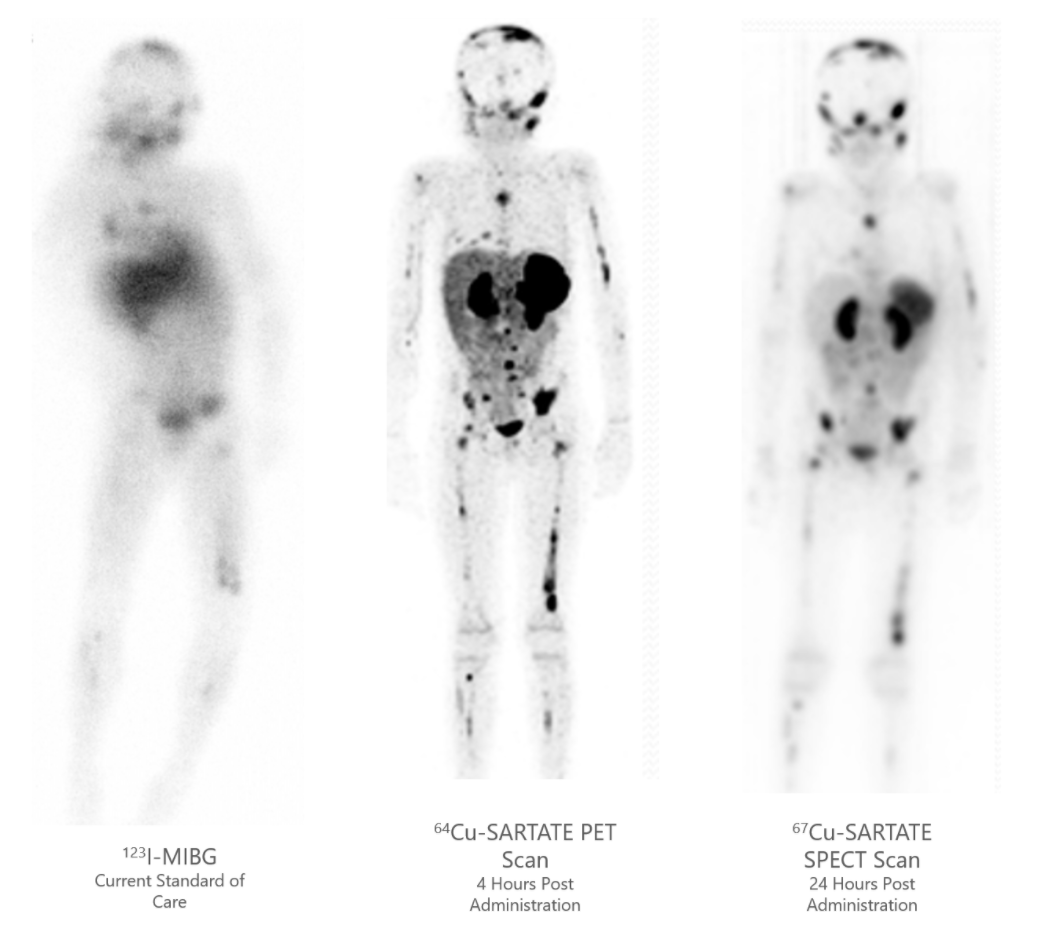

Model 295 AC Hipot Tester | SCI - an Ikonix Brand, NorthStar Medical Radioisotopes Enters U.S. Supply Agreement

NorthStar Medical Radioisotopes Enters U.S. Supply Agreement東京ディズニーリゾート 35周年 アニバーサリー・セレクション -東京ディズニーリゾート 35周年 Happiest Celebration! - [DVD]